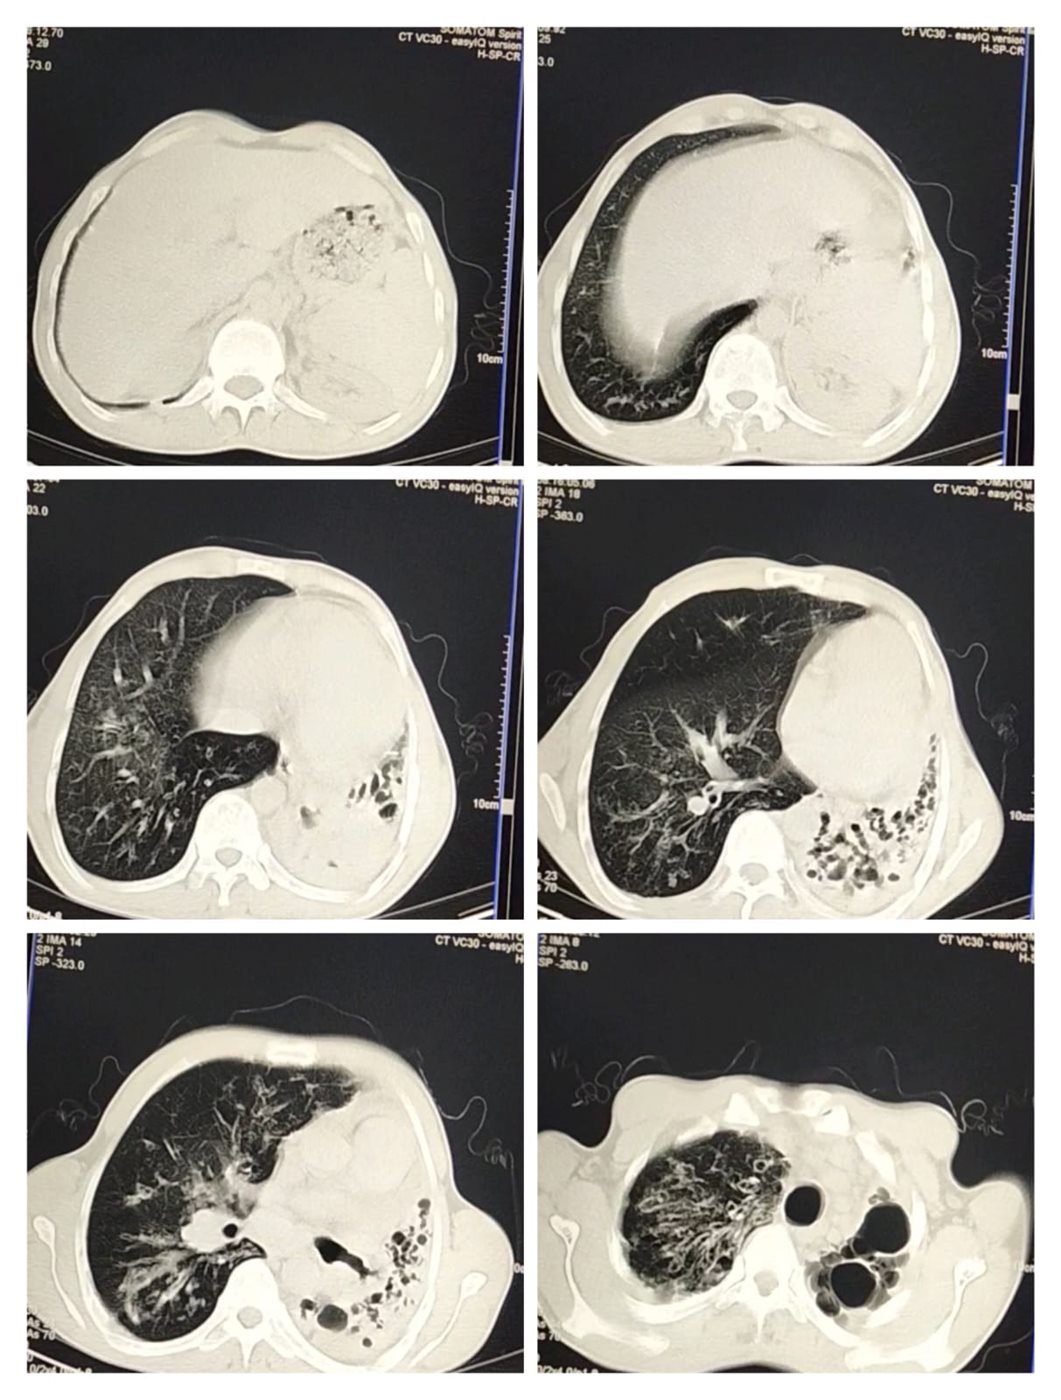

وأكمل محمد إبراهيم محمد سلطان، مريض التليف الرئوي بالشرقية: الدكاترة قالولي لازم تفضل على الأكسجين وممنوع التعرض لـ الروائح والإجهاد، وفعلًا وقفت شغل من سنة 2020، مضيفًا: الرئة الشمال توقفت عن العمل ومتليفة بشكل كامل، والرئة اليمين شغالة بنسبة 30%، أنا كنت شغال استورجي موبيليا وكان عندي ورشة، والآن عايش على معاش والدي، لإني أجلس على مولد أكسجين بالمنزل، ومحتاج لعملية زراعة رئتين.